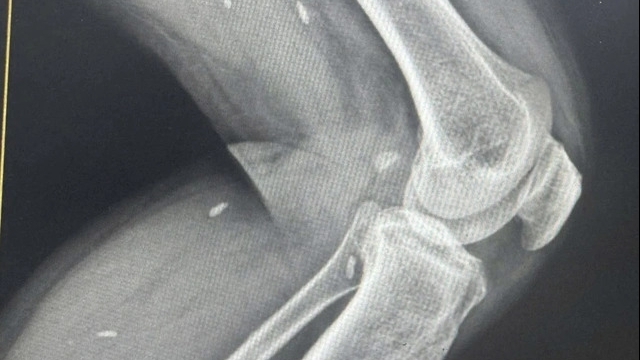

![]() |

2 viên bi được cấy vào thân dương vật sát quy đầu của người bệnh